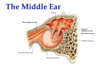

3 bones of the inner ear?

The ____ cavity contains auditory ____ (bones) which connect the __________ to the _________.

the tympanic cavity contains auditory ossicles which connect the tympanic membrane to the oval window of the inner ear.